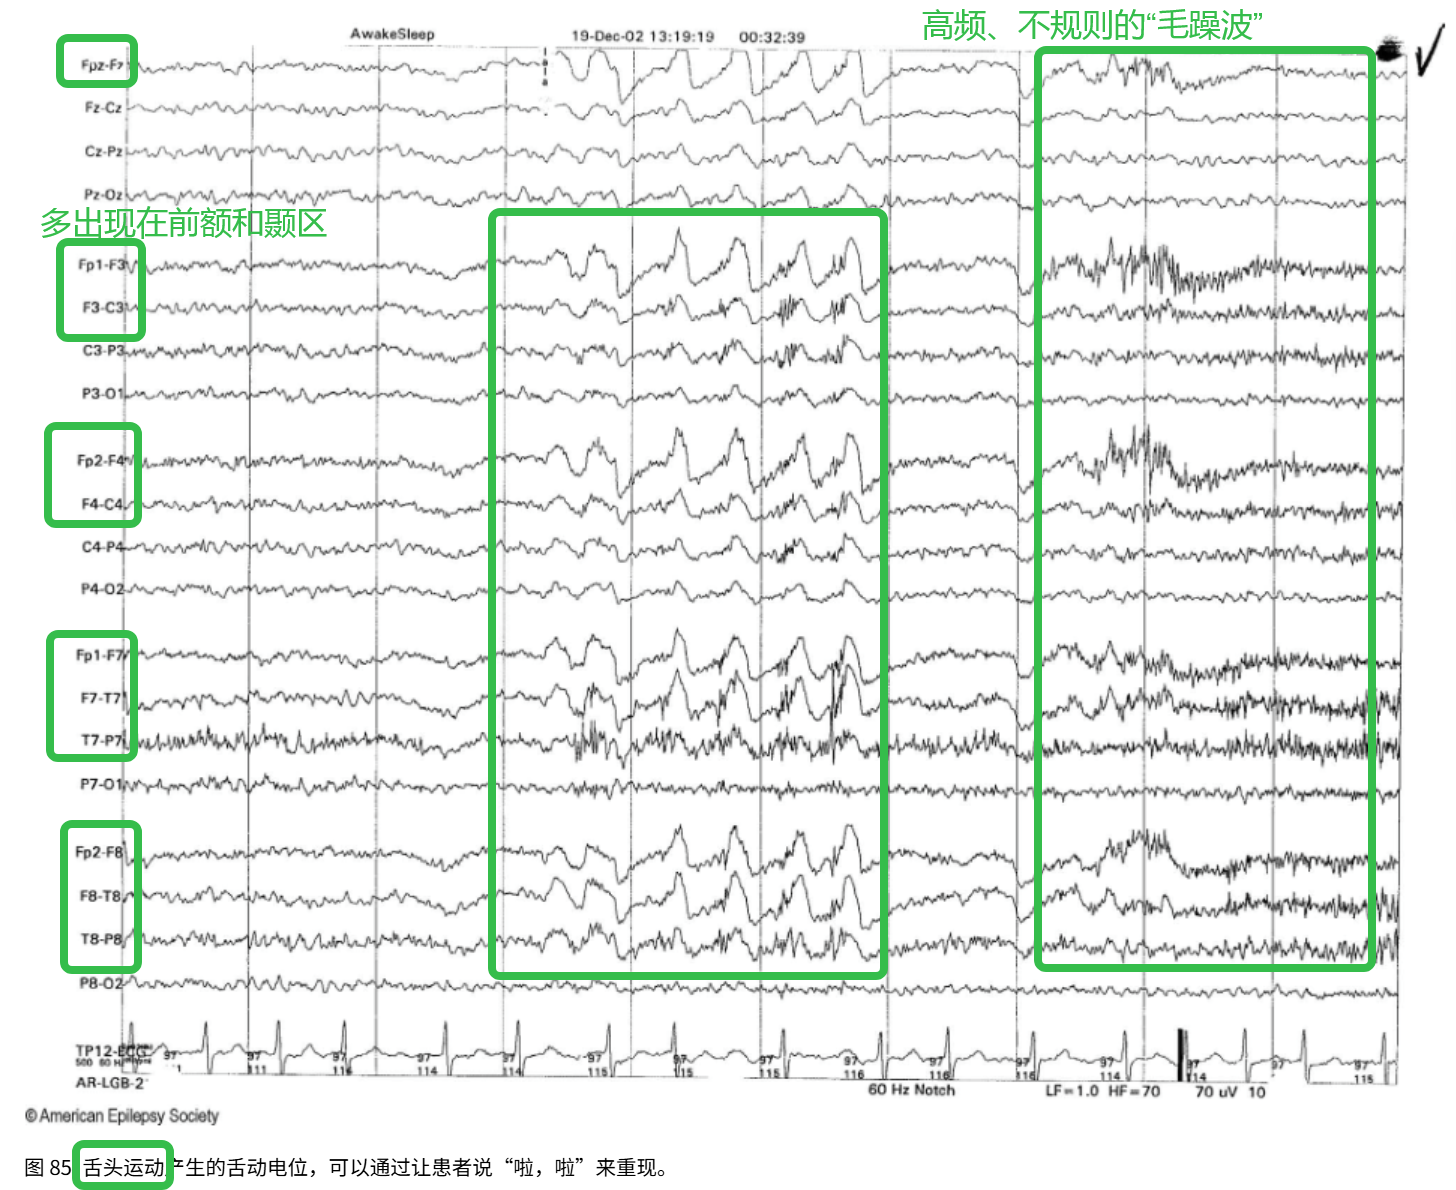

(3)舌动电位

特征:高频、无规律的“毛躁波”

区域:多出现在前额以及颞区

波型:高频β波在这里插入图片描述